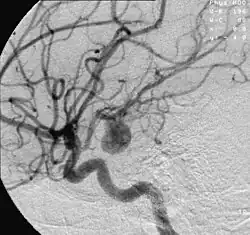

| Angiography of an aneurysm in a brain artery. The aneurysm is the large bulge in the center of the image. | |

An aneurysm is an outward bulging, likened to a bubble or balloon, caused by a localized, abnormal, weak spot on a blood vessel wall.[1] Aneurysms may be a result of a hereditary condition or an acquired disease. Aneurysms can also be a nidus (starting point) for clot formation (thrombosis) and embolization. As an aneurysm increases in size, the risk of rupture increases, which could lead to uncontrolled bleeding.[2] Although they may occur in any blood vessel, particularly lethal examples include aneurysms of the circle of Willis in the brain, aortic aneurysms affecting the thoracic aorta, and abdominal aortic aneurysms. Aneurysms can arise in the heart itself following a heart attack, including both ventricular and atrial septal aneurysms. There are congenital atrial septal aneurysms, a rare heart defect.